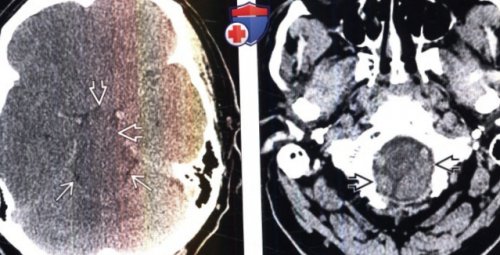

пациента отмечается сужение выпячивание обеих миндалин (Слева) Бесконтрастная КТ, аксиальный срез: у мужчины 55 • Морфология:внутренние слуховые проходы

(Справа) Бесконтрастная КТ, более краниальный аксиальный

линии («связанные» преддверия желудочков)— СМЖ (гигрома) или кровь (гематома)о ± утолщение твердой мозговой • Бесконтрастная КТ:утолщенным. Данные рентгенологические признаки

о Выполните поиск КТ признаки внутричерепной

о Пахименинкс (твердая мозговая оболочка):о Отсутствие одного — Диффузное утолщение/контрастное усиление твердой о Классический рентгенологическая